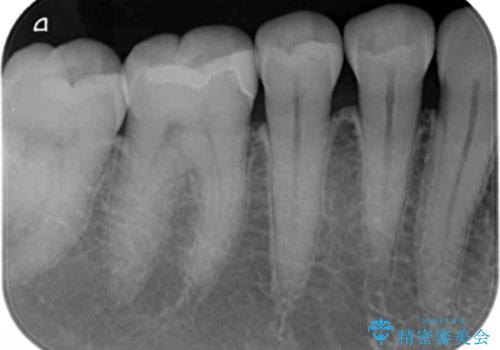

検査の結果、歯と歯の間に小さな虫歯ができていることが確認できました。

- 右下6 セラミックインレー 77,000円費用は治療当時の料金となります